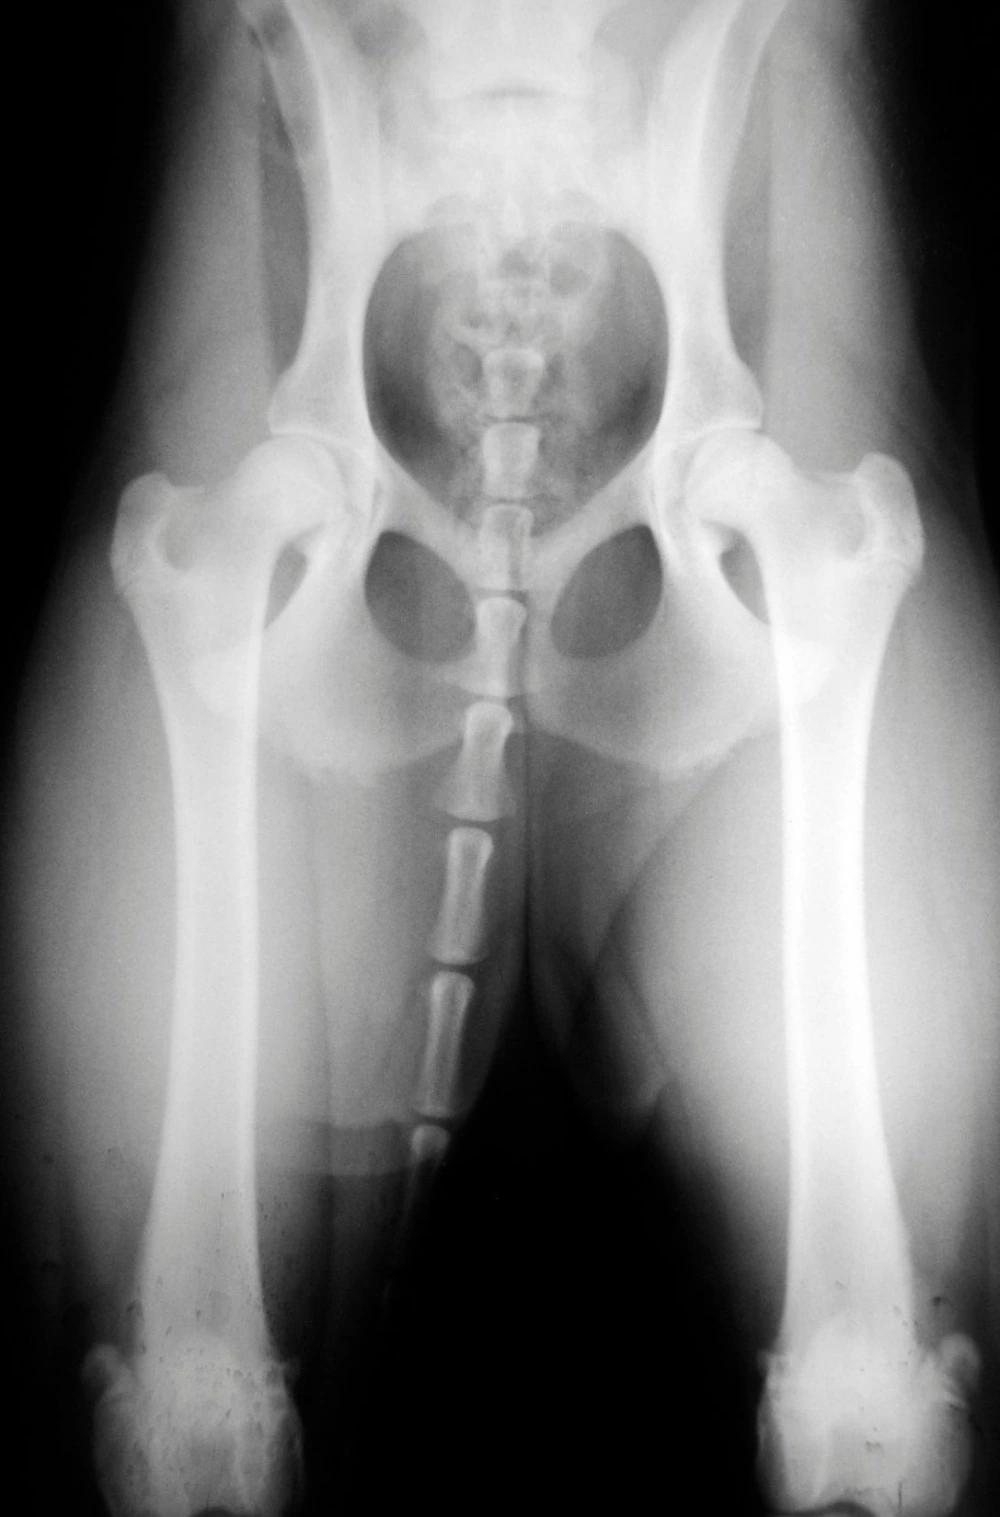

A radiografia é fundamental na medicina veterinária para diagnosticar uma série de problemas de saúde nos animais de estimação, incluindo a pata dos cachorros.

Esse exame permite avaliar os ossos, articulações e tecidos moles da pata, identificando possíveis fraturas, lesões ou problemas ortopédicos.

A radiografia pata de cachorro é uma ferramenta essencial para o diagnóstico precoce de doenças ósseas, como fraturas, displasia e tumores.

Além disso, auxilia no acompanhamento de tratamentos ortopédicos, possibilitando ajustes conforme a evolução do quadro clínico do animal.